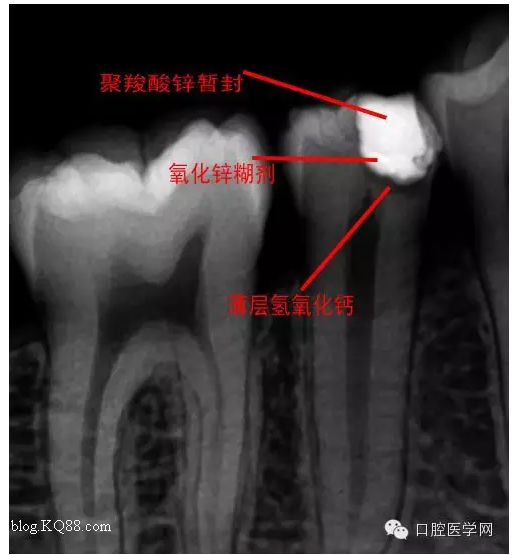

去腐,備洞。發(fā)現(xiàn)已經(jīng)露髓。根據(jù)年輕恒牙保存活髓治療原則。選擇直接蓋髓術(shù)?;颊呤俏业闹种辣4婊钏璧闹匾?,所以只是做了簡單的溝通。如果其他病人遇到這種情況術(shù)前溝通很重要。首先灌輸保髓的重要性,告知術(shù)后反應(yīng),以避免不必要的麻煩

術(shù)后第二天問小伙:什么反應(yīng)?答:輕微脹痛,無冷熱痛,無咬合痛。我驚愕因?yàn)榛卮鸬膲驅(qū)I(yè)。不愧是金牌助手。呵呵,如果病人這樣回答您會???在啰唆幾句:操作中無菌是關(guān)鍵。從露髓的一刻起就不應(yīng)與唾液接觸。去腐后生理鹽水沖洗窩洞,但不要加壓或生理鹽水棉球輕輕擦拭窩洞。柔風(fēng)吹干